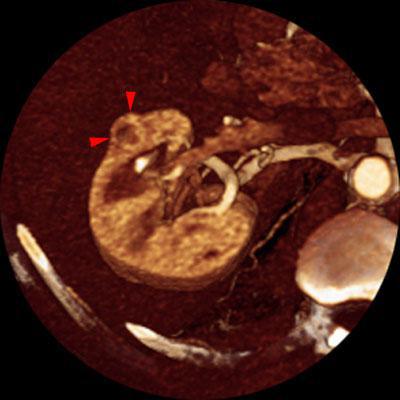

Nefrectomía parcial. Tumorectomia